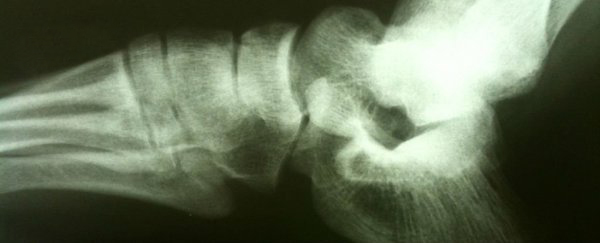

给小白鼠注射干细胞过后八周,研究人员们开始检查168只接受治疗的小白鼠和156只控制组小白鼠的股骨、胫骨和肱骨骨折情况。

在控制组小白鼠百分之百会出现某种骨折的情况下,接受治疗的小白鼠肱骨骨折减少了百分之六十九、股骨骨折减少了百分之八十九、胫骨骨折减少了百分之七十九。研究人员们发现接受治疗的小白鼠总体骨折率减少了百分之七十九。

研究人员们还对这些骨头进行了拗力测试并分析了它们的结构与组成。